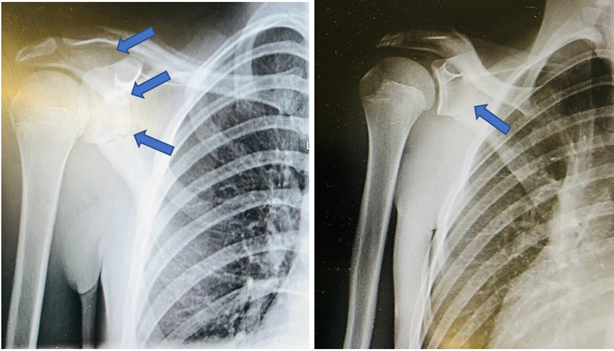

After evaluation by the medical team at the event he was evacuated to a nearby hospital. The medical team suspected a clavicle fracture, immobilized his right shoulder and gave him intravenous analgesia. He remained stable during transport. At the hospital the shoulder X-ray revealed a fracture of the neck of the scapula. He had no other associated injuries such as haemothorax or pneumothorax. He was indicated for immobilization for 4 weeks with a sling and re-evaluation at the pediatric hospital in his residence area (Figures 1 & 2).

In this case, the patient was young, which is unusual for this type of injury. Besides, his fracture was in the neck of the scapula and in literature only 25% of scapula fractures are described as neck fractures.5